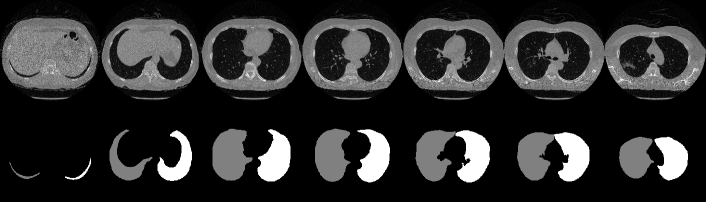

We used a publicly available pretrained lung segmentation network, U-net-R231 [29], to segment lung regions from each 3D stack of CT slices. We used the COVID-19 dataset [36] to evaluate the lung segmentation performance. The intersection of the ground truth for the 3D lung region with the U-net-R231 prediction was evaluated using the intersection over union (IoU) and Dice score and averaged across slices and stacks, obtaining the results listed in Table B. Compared with the performance evaluation results using the datasets in [29] (i.e., lung tissue research consortium––LTRC [37], lung CT segmentation challenge 2017––LCTSC [38], and vessel segmentation in the lung 2012––VESSEL12 [39]) also shown in Table B, U-net-R231 provides a high Dice score, thereby validating its excellent lung segmentation ability. Fig. F shows results of lung segmentation by U-net-R231 to illustrate its excellent performance.